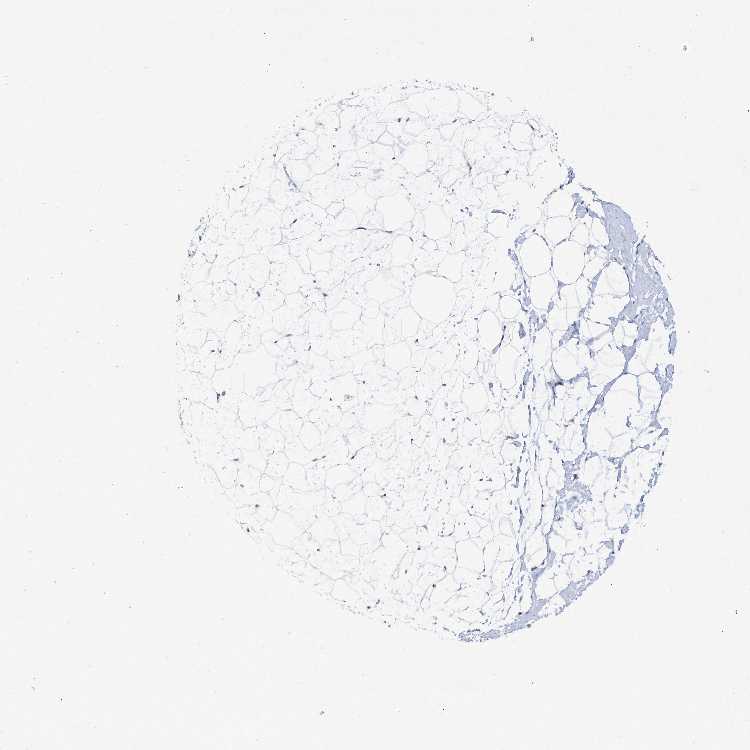

TISSUE PRIMARY DATA BREAST Show tissue menu

Breast

BREAST - Expression summary

Protein expression

Breasti

On the top, protein expression in current human tissue, based on all annotated cell types, is reported with the units not detected (n), low (l), medium (m) and high (h). Underneath, protein expression in each annotated cell type are reported using the same units.

Protein expression data is based on knowledge-based annotation. For genes where more than one antibody has been used, a collective score is set.

BREAST - Antibody stainingi

Antibody staining in the annotated cell types in the current human tissue is reported as not detected, low, medium, or high, based on conventional immunohistochemistry profiling in selected tissues. This score is based on the combination of the staining intensity and fraction of stained cells.

Each image is clickable and will lead to virtual microscopy that enables deeper exploration of all samples and also displays staining intensity scores, fraction scores and subcellular localization as well as patient and tissue information for each sample.

Antibody HPA038552Antibody HPA038553Antibody HPA040433

Adipocytes Not detectedNot detectedNot detected

Glandular cells HighLowNot detected

Myoepithelial cells HighNot detectedNot detected